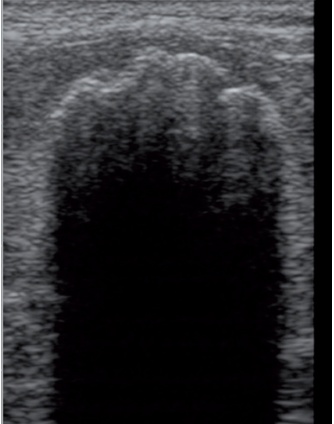

골수외조혈(EMH)과 lymphoid hyperplasia도 비장비대를 보이며, 정상적인 에코성을 보입니다(그림 7). 몇몇 환자에서는 국소적인 결절이나 직경이 0.7~3cm의 저에코성의 종괴를 보입니다. 다른 환자에서는 얼룩덜룩한 모양의 저에코성 실질이 보이기도 합니다.

고양이에서 “좀 먹은(moth-eaten)” 모양의 얼룩덜룩한 비장의 모양은 정상 고양이에서도 나타나며, 다른 병적 상황인 lymphoid hyperplasia, EMH, 수동적 울혈(passive congestion), carcinoma, histiocytic sarcoma, 비만세포 침윤과 granulomatous splenitis에서도 나타날 수 있습니다.2), 5), 6), 7)